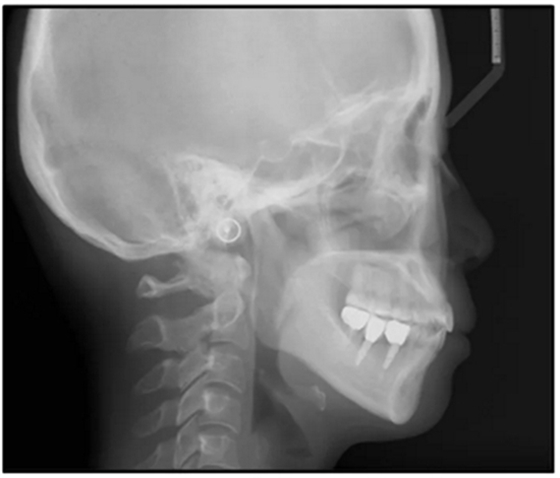

36歲;女性;尋求下頜左后方區(qū)域間隙管理的建議(圖1和圖2),通過(guò)治療獲得了良好的牙頜面效果(圖3和圖4)。她被診斷患有骨性I類和代償性牙性II類錯(cuò)合畸形,并且上頜左側(cè)尖牙缺失(圖1和2)。大約七年前,由于不可修復(fù)的齲齒,拔除了下頜左側(cè)第一和第二磨牙(圖5)。37相鄰的第三磨牙向近中移動(dòng)并傾斜入間隙,導(dǎo)致無(wú)牙頜間隙減小至約14 mm(圖2和圖5)。臨床和影像學(xué)評(píng)估顯示多發(fā)性齲損和在下頜右側(cè)567處有一不良的固定橋修復(fù)體(圖1和5)。此外,下頜左中切牙缺失,造成下頜中線向左側(cè)偏移約3 mm(圖1和圖2)?;颊咦栽V,她的右上第一前磨牙和左上尖牙在13歲時(shí)由其家庭牙醫(yī)拔除,因?yàn)樗鼈儽蛔枞筋a側(cè)萌出(圖1)。上頜第二磨牙缺失(未知病因),并且相鄰的第三磨牙已經(jīng)轉(zhuǎn)移到第二磨牙間隙中。如補(bǔ)充材料所示,美國(guó)正畸學(xué)差異指數(shù)DI是28分。種植體部位(下頜左側(cè)和右側(cè)第一磨牙)由于復(fù)雜性得到額外4分(補(bǔ)充材料)。

總之,這種復(fù)合錯(cuò)合畸形是一個(gè)很嚴(yán)重的問(wèn)題,需要進(jìn)行認(rèn)真的多學(xué)科序列治療。治療后X光片(圖6)和重疊頭影測(cè)量圖(圖7)記錄了跨學(xué)科治療結(jié)果。

圖5. 治療前的側(cè)位片(上圖)和全景(下圖)的X光片